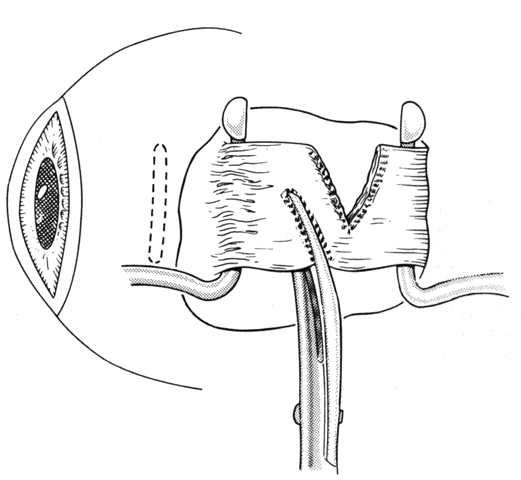

If a rectus muscle has been recessed 5 mm or more, further recession will put the new insertion at or beyond the arc of contact of the rectus muscle and the globe. This may cause decreased function of the muscle and produce noncomitant ocular rotations, especially in extreme gaze positions. To weaken a rectus muscle without disturbing its insertion site, a marginal myotomy can be performed.39,40 Usually, two separate cuts are made into the muscle near the tendon (Fig. 36) until the muscle lengthens. The weakening effect can be graded by increasing the number of cuts from two to three or by increasing the percent of the muscle that is cut. To be effective, a marginal myotomy should be accompanied by resection of the ipsilateral antagonist muscle.

Fig. 36. To perform a marginal myotomy, the muscle tendon is gently stretched between two Jameson muscle hooks. Prophylactic hemostasis is achieved by clamping the muscle or by application of a wet-field cautery to blanch the vessels in the tendon. The muscle is cut with small “snips” using a Wescott scissors.

If a muscle tendon has been split during mobilization of the tendon or by passing a muscle hook under a scarred tendon, the marginal myotomy should be avoided. Placing cuts in the muscle may cause the muscle to be transsected (Figs. 37 through 40).

Fig. 37. When a muscle is split, a marginal myotomy is contraindicated.

Fig. 38. The split muscle is clamped.

Fig. 39. The cuts in the muscle divide it.

Fig. 40. The muscle can retract into the orbit.